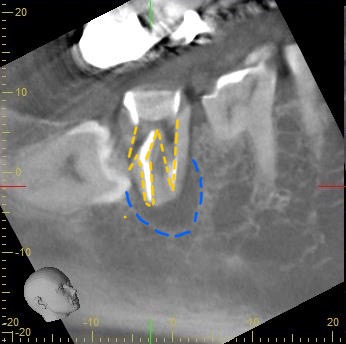

次に治療前のデンタル、CT写真をご覧下さい。

黄色い部分が治療によって拡大された根管なのですが、左側に1部大きく斜めに空けられてしまっている部分があるのがわかると思います。

これはパーフォレーションと言って歯の根管の壁に穴が空いてしまうことを言います。

歯の根っこの周囲には「歯根膜」という血管を豊富に含んだ組織が存在します。歯根部にパーフォレーションを起こすとまずは空いた穴より出血が見られます。そこに細菌感染が起こることで痛みが出たり歯茎が腫れることがあります。また痛みなどが出ずに経過が長期になると、周囲の骨が溶けてしまいます。

青い部分が溶けた骨の部分でレントゲンでは黒く写ります。

ですが今回は回復の見込みがあると判断し、パーフォレーションリペアを行います。